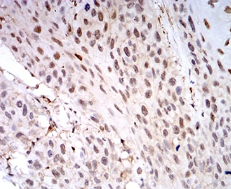

IHC    1/200 - 1/1000